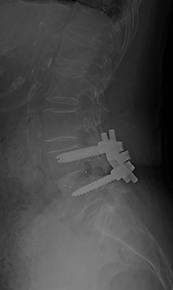

第4腰椎の前方へのすべりのため神経の圧迫を認めています。腰椎後方からずれを金属で整復固定し神経症状が改善しています。

階段状に腰椎が変性すべりをおこしている症例

【術前】

第2, 第3, 第4腰椎に前方への変性すべりを認めます。痛みのため背中を反って立てないことが分かります。MRIではいずれの椎間でも強い脊柱管狭窄が発生し、神経が圧迫されているのが分かります。

【術後】

スクリューとロッド、人工骨を使用した手術により腰椎の階段状変性すべりが整復され、痛みが改善したため腰を反って立つことが出来ています。第2腰椎の前方すべりは軽微であったため、金属は使わず除圧術のみに留めています。